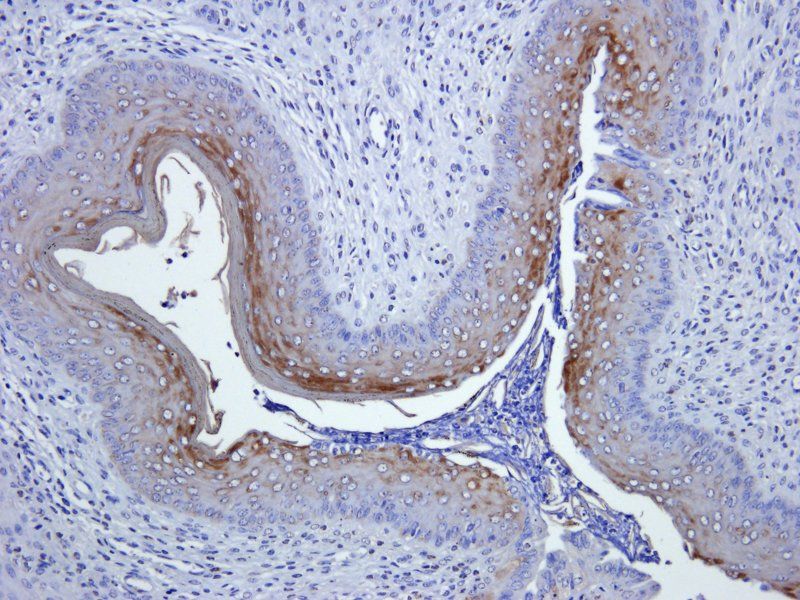

ELISA, ICC, IF, IHC-P

KLH conjugated synthetic peptide derived from human Ly-6G. Please contact us for the exact immunogen sequence. The peptide is available as orb374942.